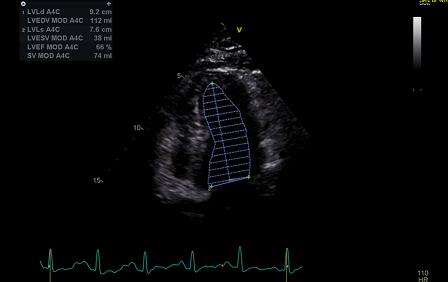

术前超声心动图

诊断:缩窄性心包炎、左室舒张功能减低、右室舒张功能减低。